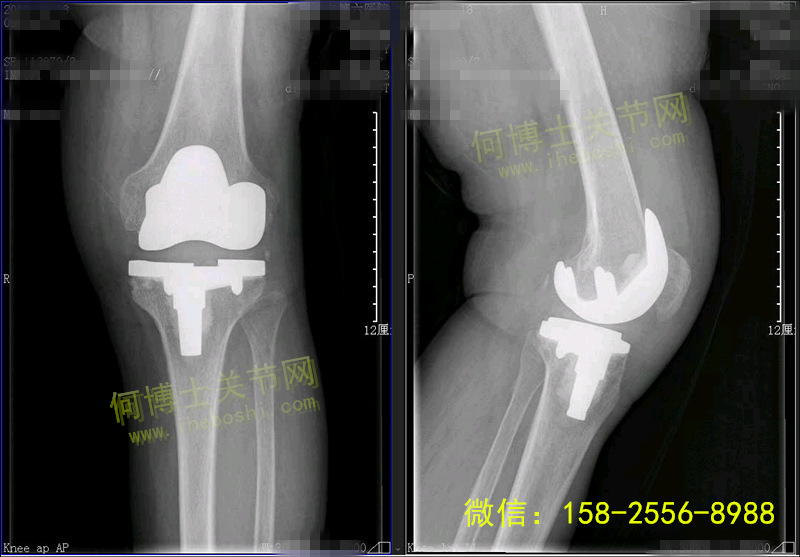

术后片子:假体在位稳定

20180605163889988998.jpg